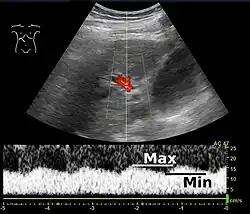

Doppler ultrasonography of the portal vein over 5 seconds, showing peaks of maximal velocity, as well as points of minimal velocity.

Portal vein pulsatility can be measured by Doppler ultrasonography. An increased pulsatility may be caused by cirrhosis, as well as increased right atrial pressure (which in turn may be caused by right heart failure or tricuspid regurgitation).[9] Portal vein pulsatility can be quantified by pulsatility indices (PI), where an index above a certain cutoff indicates pathology:

Average-based (Max - Min) / Average[9] 0.5[9]

Max-based (Max - Min) / Max[11] 0.5[11][12] - 0.54[12]